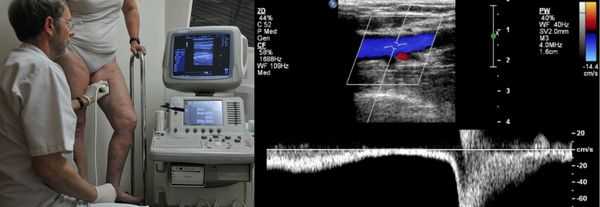

Проведение диагностики ХВН на ранних стадиях способствует ускорению лечения. При диагностике важно определить стадию заболевания. После общего клинического осмотра врач проводит дуплексное ангиосканирование вен нижних конечностей, чтобы определить тактику лечения. Дуплексное ангиосканирование поможет оценить состояние исследуемых сосудов, увидеть места их сужений или расширений, а также выявить тромбообразования.

Одним из самых доступных методов диагностики данного заболевания является УЗИ, главным преимуществом которого является многоразовость применения без рисков для здоровья, безболезненность, а также возможность выявить нарушения в текущей работе венозного аппарата. [3]

Для получения лучшего результата обследование рекомендуется проводить во второй половине дня. Поскольку именно после дневной нагрузки на ноги можно провести более точную оценку состояния клапанов, диаметра вен и степени поражённости стенок. На тактику лечения влияет наличие тромба в просвете вен, который приводит к нарушению тока крови и несёт наибольшую угрозу для жизни пациента.